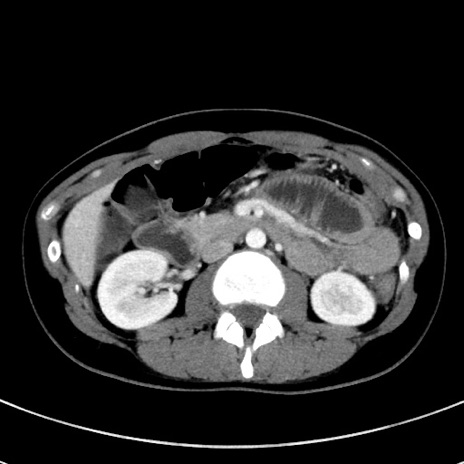

症例17(横断像)

【症例】20歳代女性

【主訴】嘔吐、下腹部痛

【現病歴】昨日夕食後に嘔吐し下腹部痛が出現。本日になっても嘔吐持続し改善しないため来院。

【身体所見】意識清明、BT 37.2℃、BP 108/67mmHg、腹部:平坦、やや硬、下腹部正中から右にかけて圧痛あり、反跳痛軽度あり、tapping pain(+)。

【データ】WBC 13600、CRP 14.94